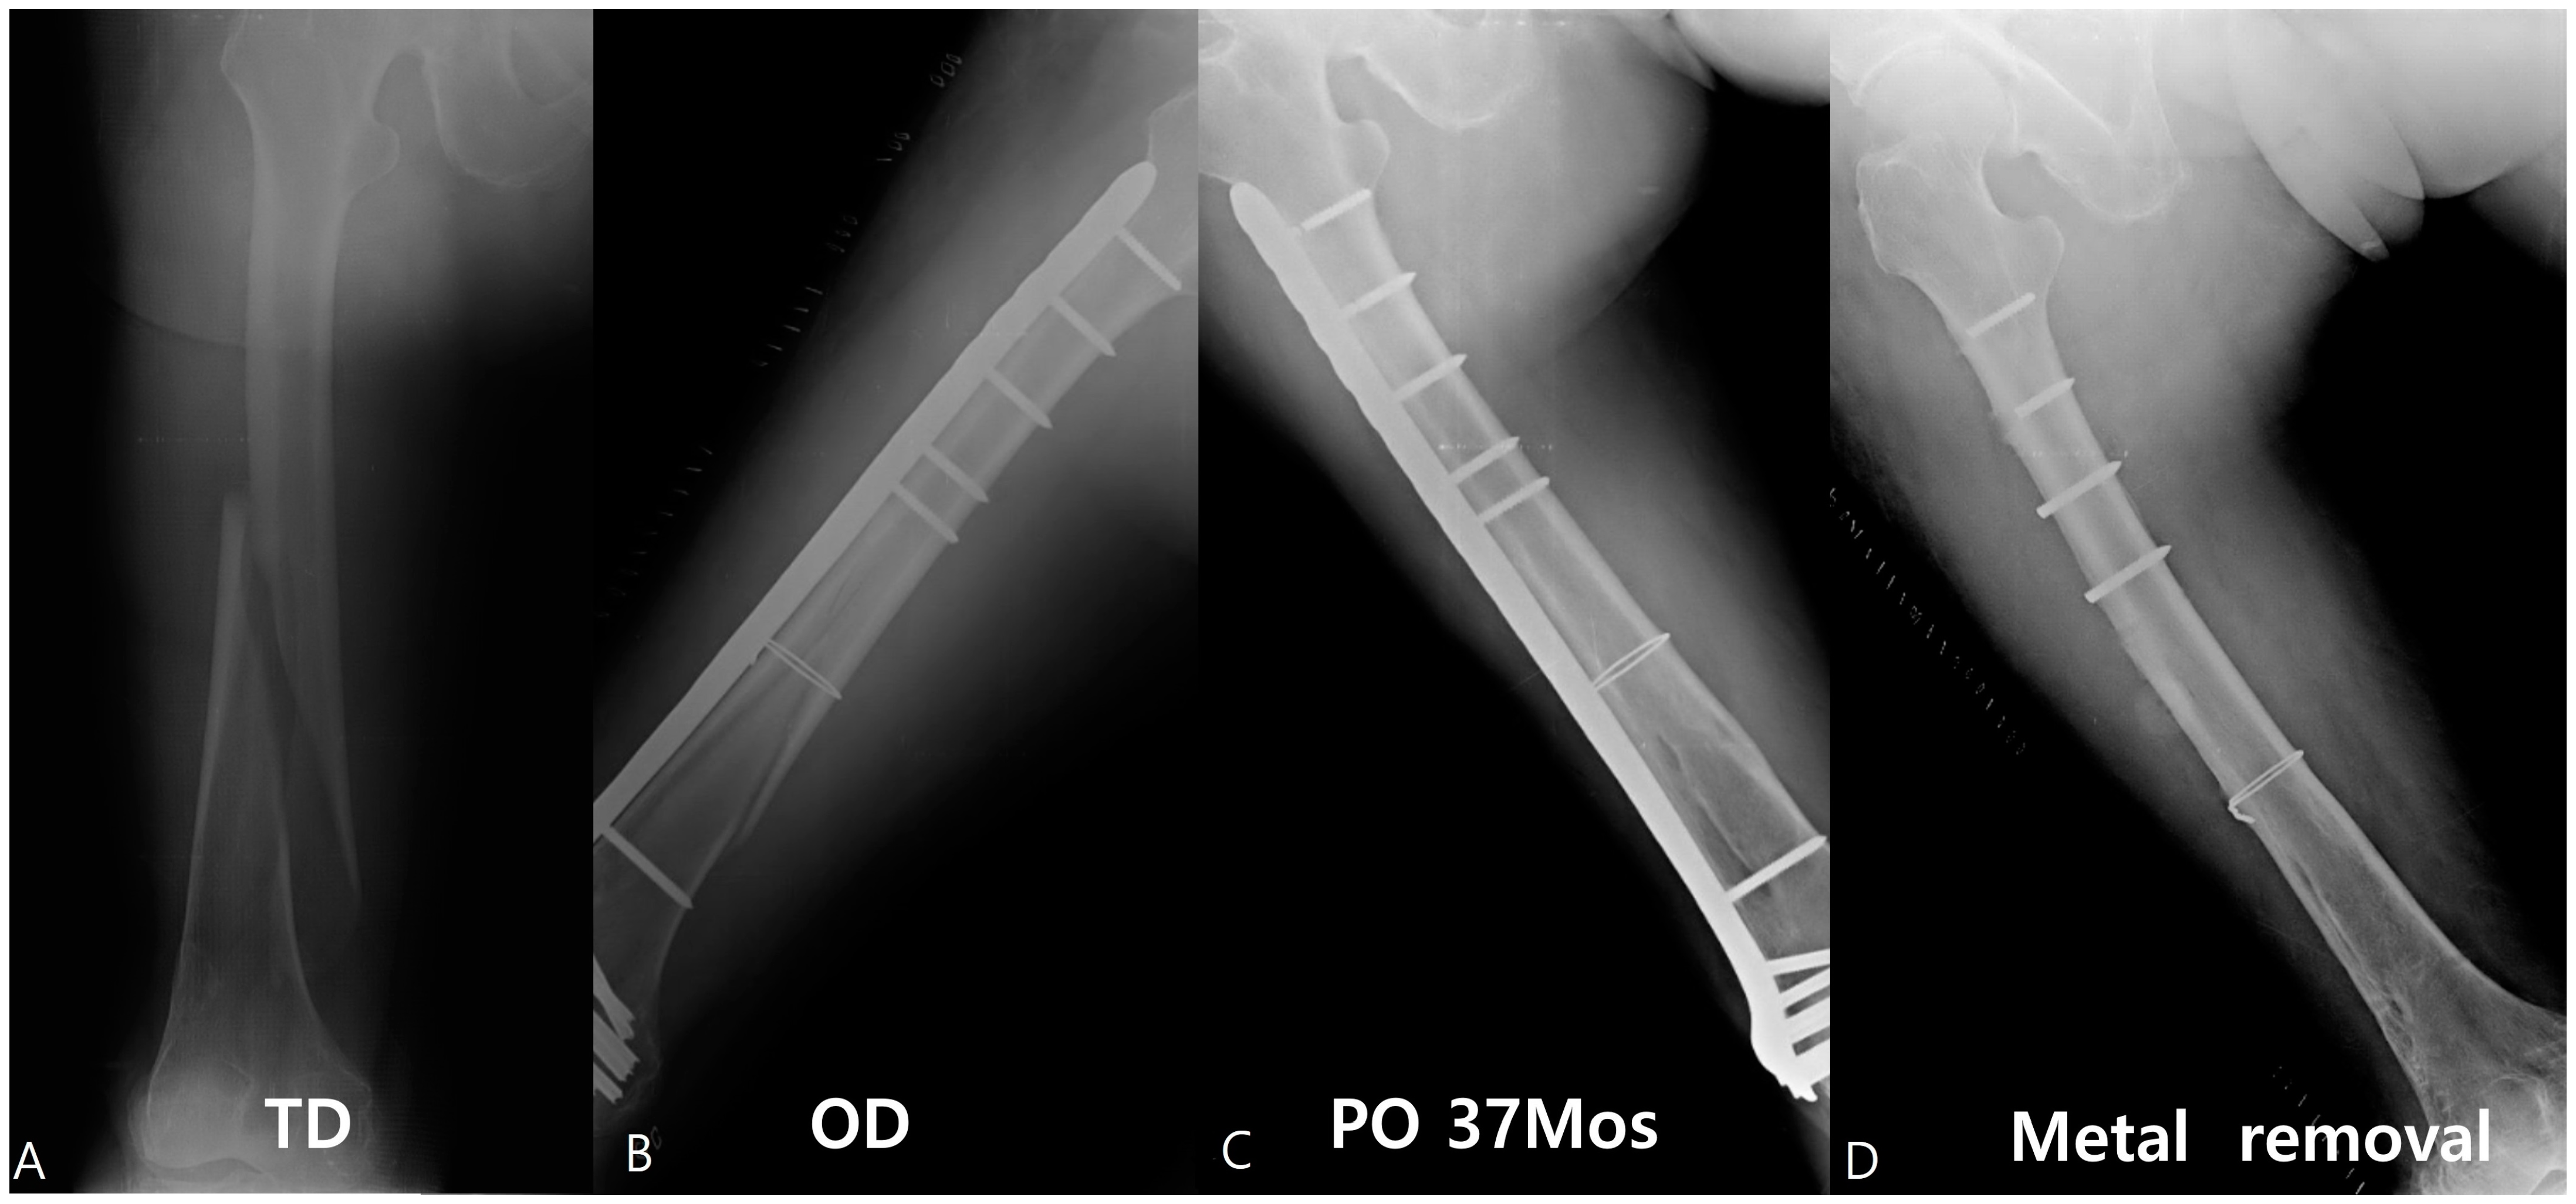

Risk Factors of Proximal Screw Breakage of Locking Plate (ZPLP®) after MIPO for Distal Femur Fractures -Analysis of Patients with Plate Removal after Bony Union-

2. Patients and Methods

2.1. Surgical Technique